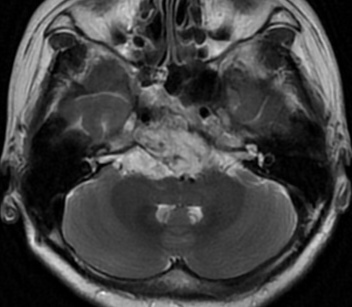

女性患者,56岁,因“视物重影4月”于2023-07-11入院。

入院诊断:斜坡脊索瘤